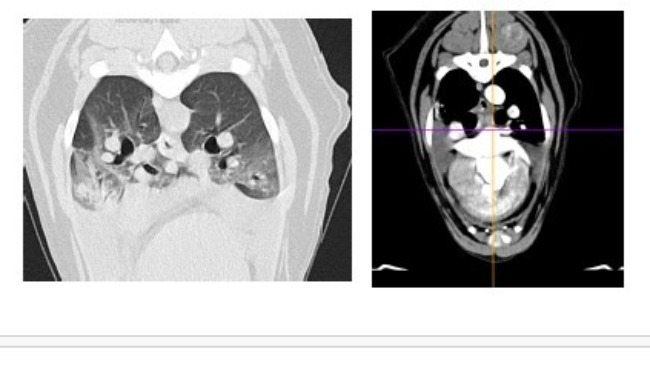

Zwykłe badanie profilaktyczne, a wyszło: podniesiony kortyzol, powiększone węzły chłonne, pobudzona śledziona i płyn w jamie opłucnowej.

Badania moczu, badanie krwi, USG jamy brzusznej, echo serca, rtg, wizyta onkologiczna.... To wszystko co już mamy za sobą i nadal nie wiadomo co się z Atenką dzieje i nie wiadomo jak ją leczyć. Wykluczony został zespół Cushinga. Wykluczone zostały choroby serca. Podejrzenie chłoniaka na razie nie zostało potwierdzone. Diagnostyka trwa dalej, a koszty rosną w przerażającym tempie. Przed nami tomografia oraz biopsja śledziony, biopsje węzłów chłonnych, badanie cytologiczne płynu z jamy opłucnej. To koszt minimum 3000 zł.